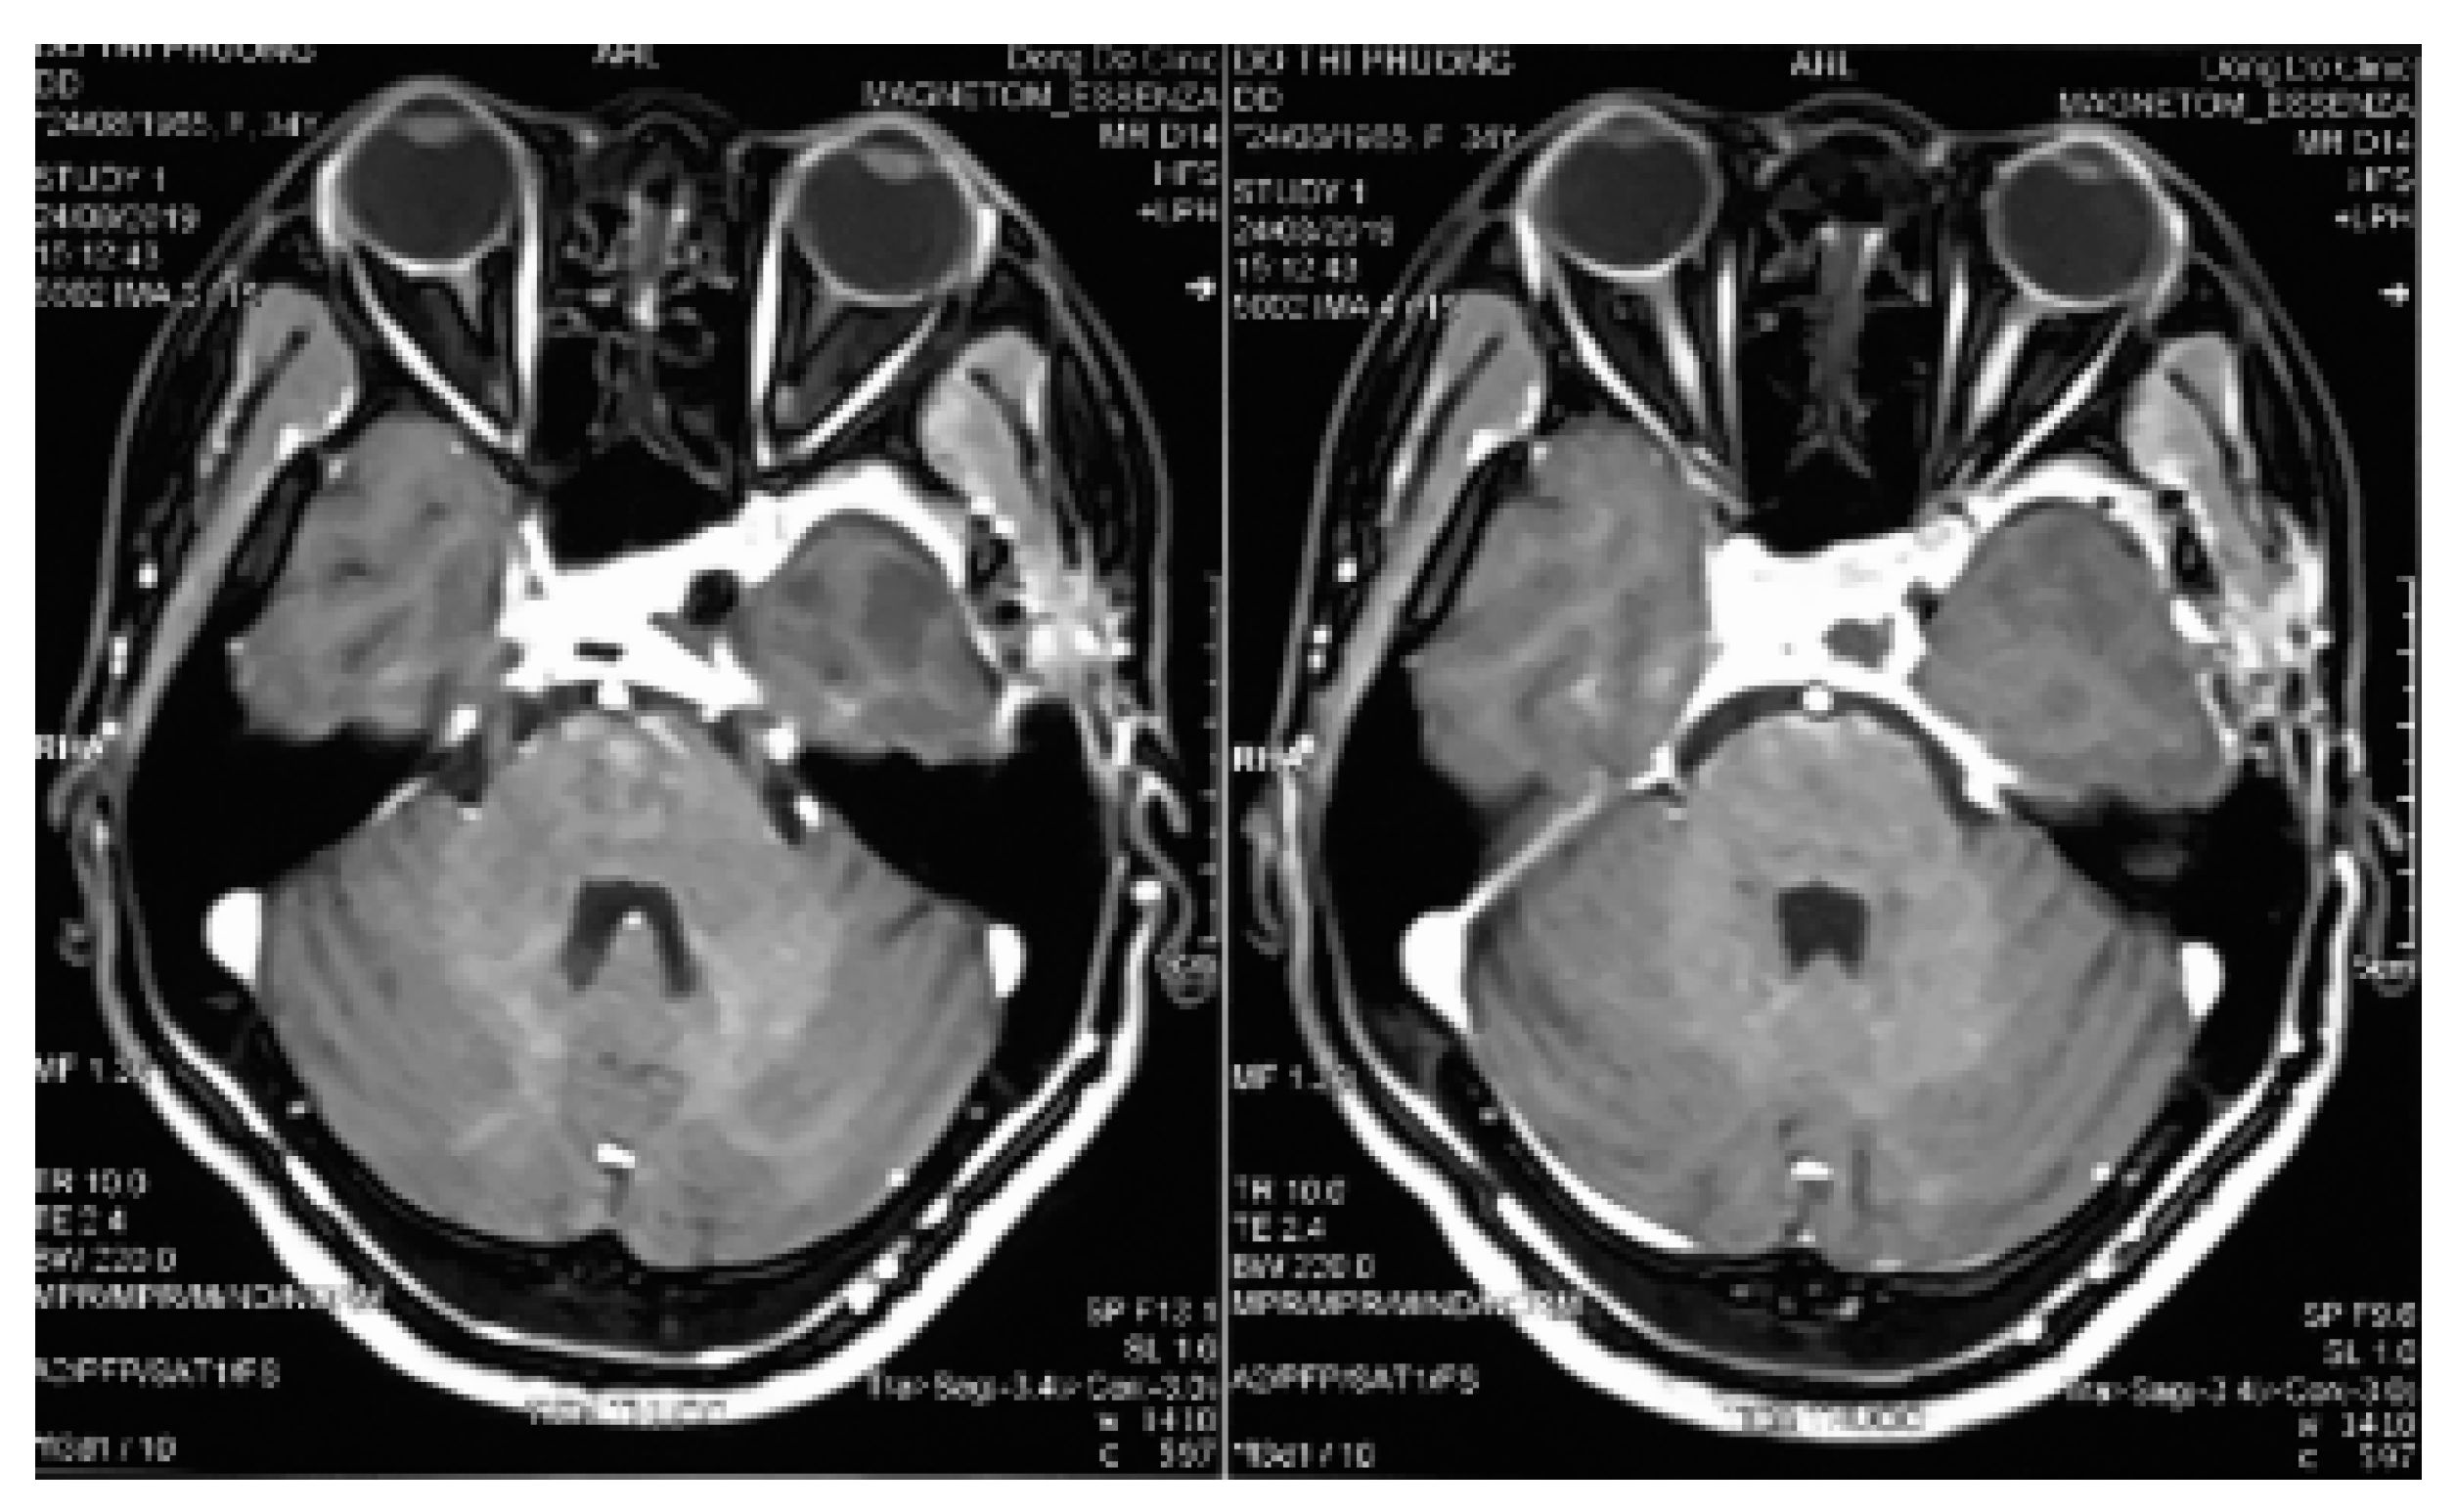

After incising the inner layer of the lateral wall of the cavernous sinus, along the path of the V2 branch nerve and partial resection this nerve, the tumor inside the sinus was exposed as a soft porous mass that was easy to bleed but it could be stopped by squeezing or spongel. The tumor could be completely dissected, and separated from the carotid artery and the sinus cavity with a blunt tool to avoid damaging the blood vessels in the sinus. Some authors suggested that CSC should be removed in bloc dissection [8,11,24]; however, this method is only suitable for small and medium tumors. For large tumors, they should be taken in small pieces (debulking dissection) to stop bleeding with pressed cotton, which will reduce blood loss and bleeding during surgery. In the places where veins flow into the cavernous sinus, after tumor resection, we used a spongel inserted into it to stop the bleeding. With the bleeding from the artery feeders, mini clips were used, and electronical coagulation was limitted due to ICA constriction. We observed that this method of hemostasis was very effective, which ensured that the surgical field was not flooded by blood, helping the dissection and resection process to be increasingly more safe and reducing blood loss. During the operation, the sinus cavity was opened in a straight line, parallel to the V2 nerve; hence, as the dissection on the arch of the sinus cavity, we had to lift the lateral wall of the cavernous sinus upward. This manipulation might have damaged the thrid nerve, leading to thrid nerve paralysis postoperatively. However, this condition was temporary, as the third nerve was almost fully recovered after acupuncture for 3 months. The phenomenon of maxillary facial numbness (corresponding to the V2 branch) has been predicted intra surgery. Postoperative magnetic resonance imaging showed that the tumor was mostly removed (Figure 4).

Figure 4.

Three-month postoperative magnetic resonance imaging.